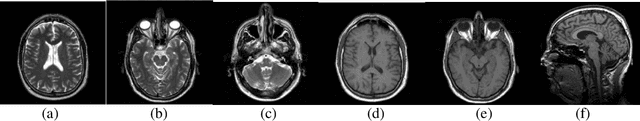

Abstract:Tumor segmentation from magnetic resonance imaging (MRI) data is an important but time consuming manual task performed by medical experts. Automating this process is a challenging task because of the high diversity in the appearance of tumor tissues among different patients and in many cases similarity with the normal tissues. MRI is an advanced medical imaging technique providing rich information about the human soft-tissue anatomy. There are different brain tumor detection and segmentation methods to detect and segment a brain tumor from MRI images. These detection and segmentation approaches are reviewed with an importance placed on enlightening the advantages and drawbacks of these methods for brain tumor detection and segmentation. The use of MRI image detection and segmentation in different procedures are also described. Here a brief review of different segmentation for detection of brain tumor from MRI of brain has been discussed.